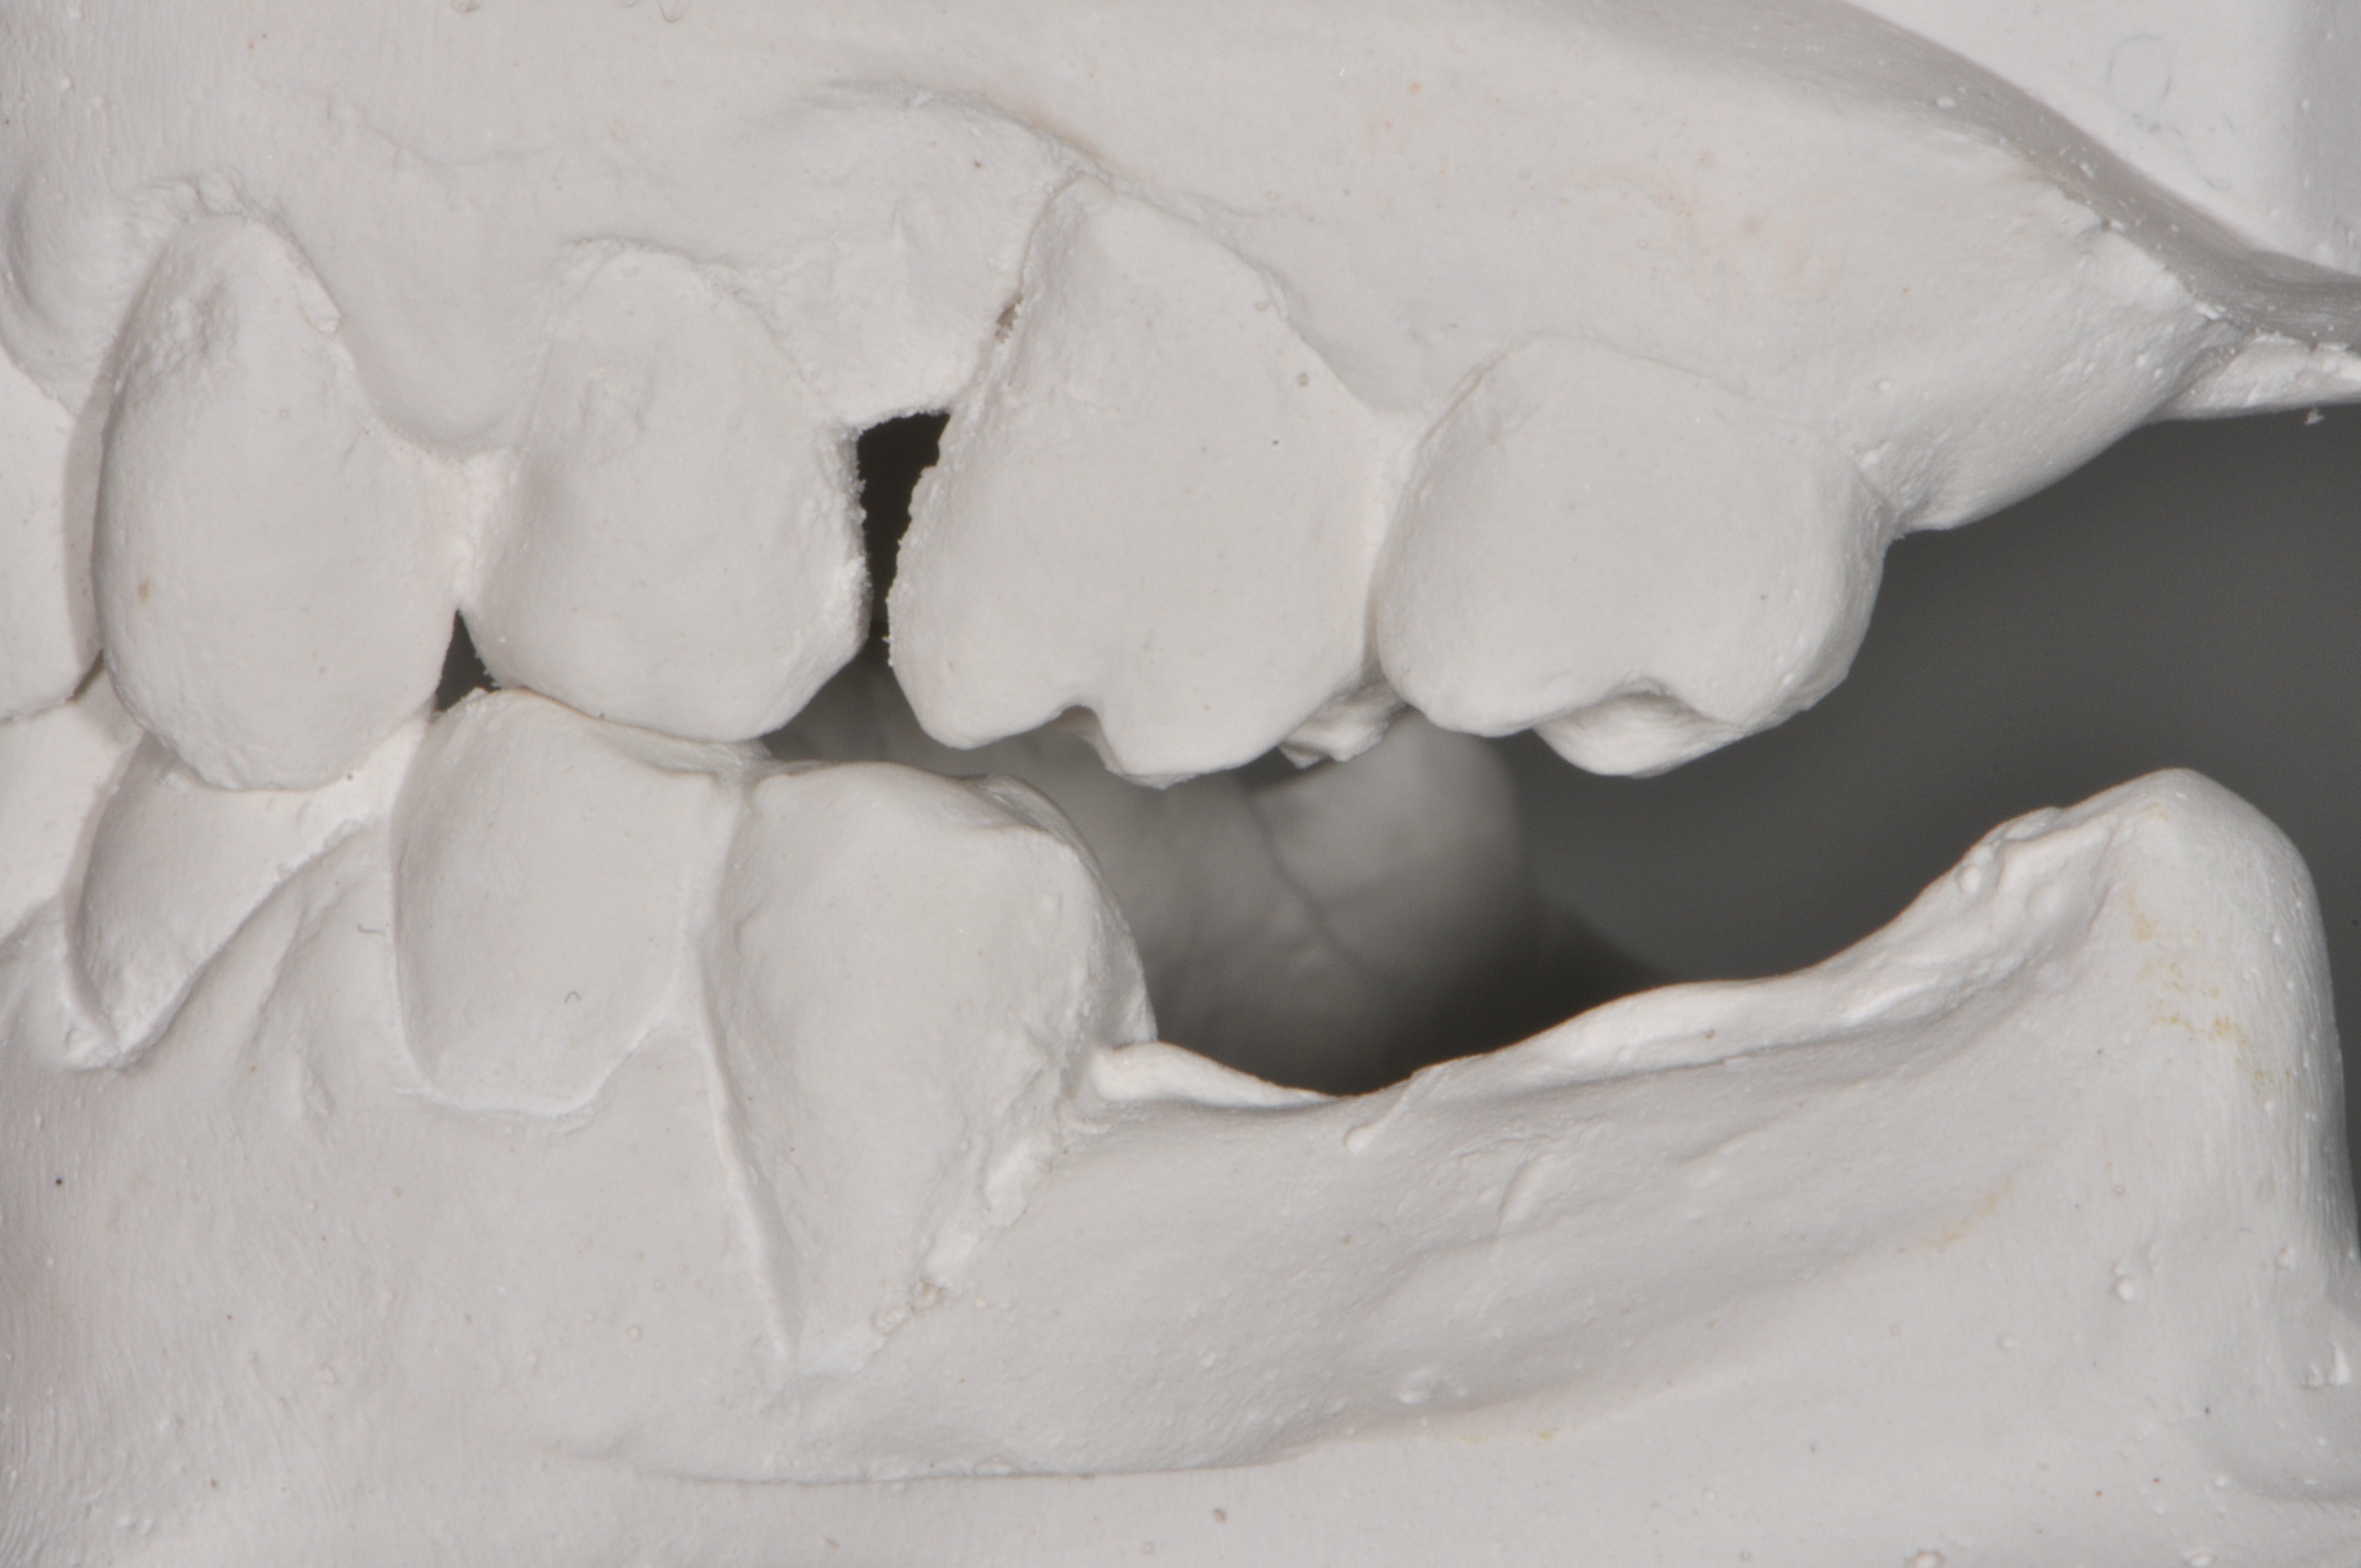

Replacement of a fixed partial denture with three implants

A 52-year-old patient is a referral and has been wearing an immediate provisional partial denture after replacement of her worn and fractured fixed partial denture. As a definitive treatment solution, the patient desired "beautiful and long-lasting" implant-supported single crowns. Clinically the CT-scan revealed a very narrow bone crest ("knife-edge") in the 3rd quadrant. Implant placement has been planned with a simultaneous GBR procedure.